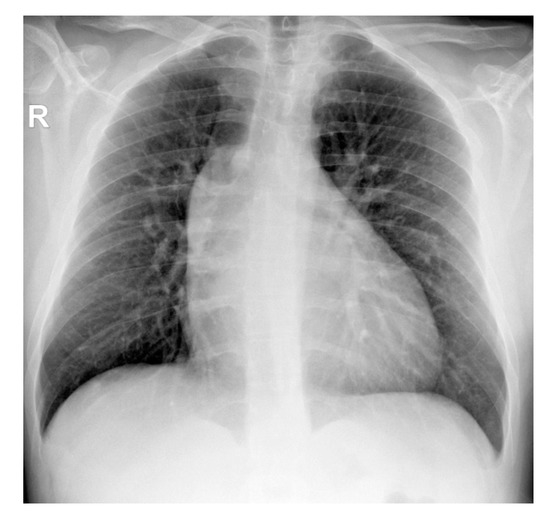

2. Case Presentation